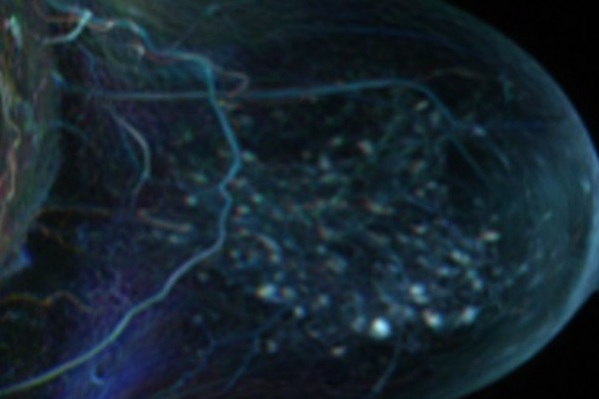

MALBACS

MALBACS (Start 2022) aims at enhancing MRI breast cancer (BC) screening for women a high risk with help of machine learning. We will develop novel approaches for personalized screening, early detection, and a reduction of false positives leading to unnecessary biopsies. It is funded by the CCC.